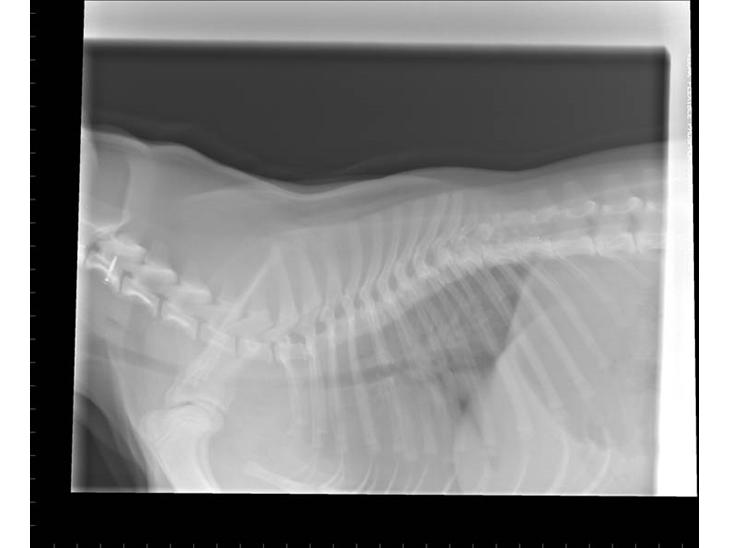

FreYa's skæve ryg + ekstra ryghvirvel.